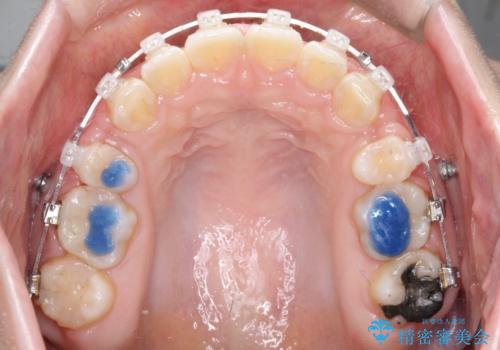

上下左右小臼歯を抜歯して審美装置で治療を行いました。

抜歯したスペースをきちんと下げることができるように、矯正用のアンカースクリューを用いて治療をしております。